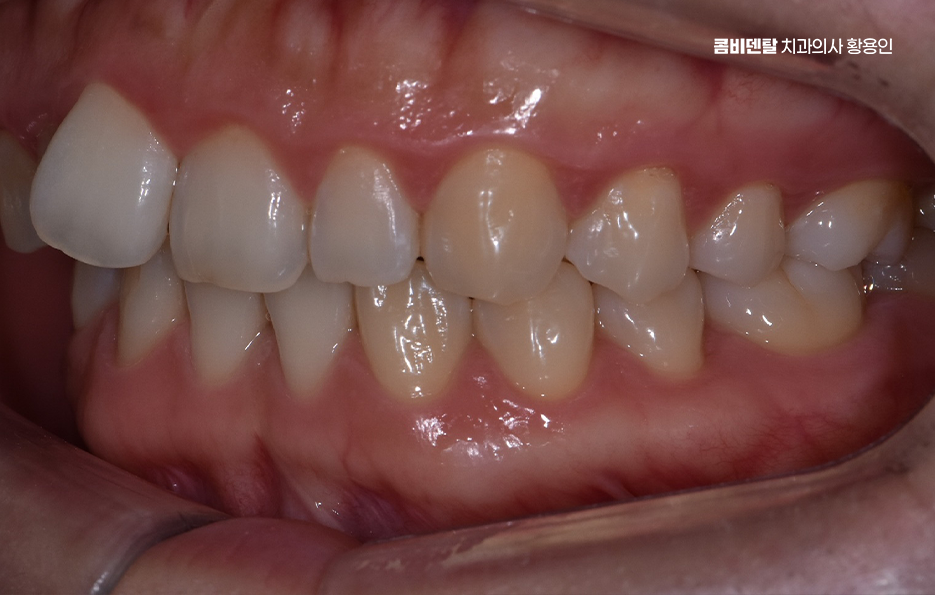

치아 교정을 할 때 통증을 느끼는 정도는 교정 치료의 방식이나 사용되는 장치, 발치 여부 등에 따라서도 차이가 있어요. 치아 교정은 치아를 이동시키면서 새로운 위치에 자리 잡도록 하는 과정이기 때문에 일정한 압력이 가해지면서 불편함이나 통증이 생길 수 있지만 이러한 통증은 시간이 지나면서 점차 완화되기 때문에 너무 걱정할 필요는 없으며 교정 치료를 받는 동안 치아교정 통증 줄이는 방법 또한 있기 때문에, 교정 과정을 좀 더 편안하게 진행할 수 있도록 여러 가지 방법을 활용하신다면 좋을 거예요

교정 통증이 발생하는 가장 큰 이유는 치아가 이동하면서 주변 조직과 신경이 자극을 받기 때문으로 치아는 잇몸 뼈와 치주 인대에 의해 고정되어 있는데, 교정 장치를 부착하면 치아가 천천히 이동하면서 치주인대에 압박이 가해지고, 이로인해 혈류량이 감소하면서 신경을 자극하는 대사물질이 생성되어 통증이 발생하고, 이 과정에서 압박되는 쪽 뼈가 녹고, 반대쪽 여유공간에서 뼈가 재 형성되면서 통증이 발생하는 거예요.

교정 장치의 종류에 따라서도 통증의 정도가 다를 수 있는데 일반적인 금속 브라켓을 사용하는 경우, 초기에는 금속이 입 안쪽에 닿으면서 불편함을 느낄 수 있어요. 특히 교정 와이어를 조절할 때마다 일정한 힘이 가해지기 때문에 몇 일 동안은 씹는 것이 불편할 수도 있지만 반면, 클리피씨 같은 자가 결찰형 브라켓을 사용하는 경우, 마찰력이 줄어들면서 치아 이동 속도가 상대적으로 빠르고, 통증이 덜하다고 느낄 수 있어요. 또한 투명 교정이나 인비절라인 같은 경우에는 탈착이 가능하고 교정기로 인한 통증이 일반교정에 비해 상대적으로 덜한 편이라는 특징이 있어요